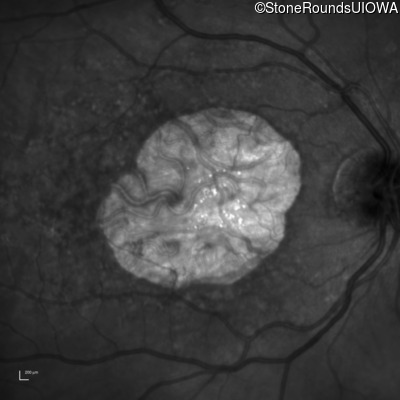

Infrared Fundus Photograph - Right - 20/125 -2

Exemplar